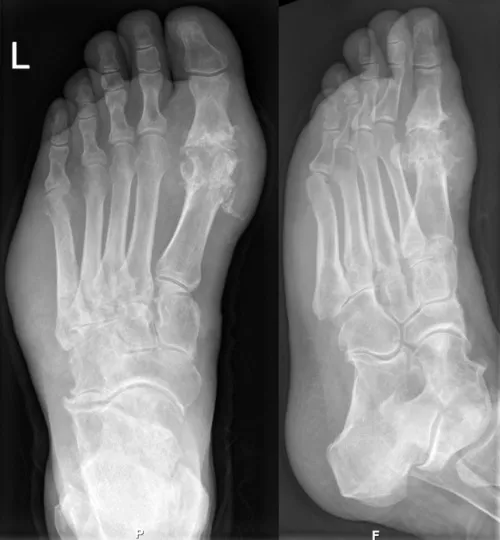

Подагра починається з високого рівня сечової кислоти в крові. Кислота утворює гострі кристали в суглобах, які імунна система сприймає як загрозу та атакує. Саме це викликає нестерпний біль.